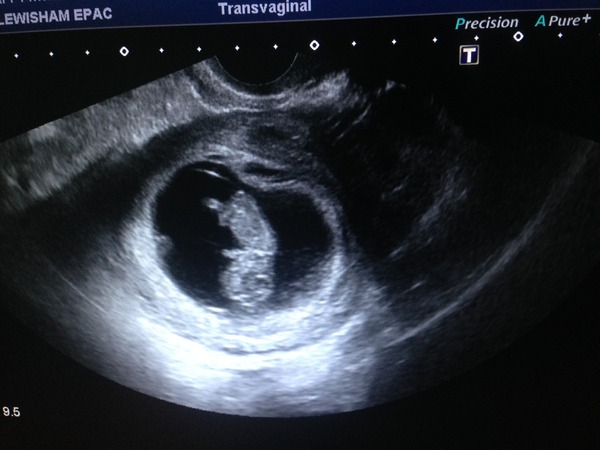

Jem01 · 09/12/2015 13:56

Hi everyone haven't posted in a while, it's been super busy at work so feeling very tired most days. Had booking appt on Monday with a lovely midwife. Unfortunately I've had more spotting this week and had another scan this morning to reassure myself. Everything fine though nurse saw blood below the sack so could explain the spotting. I think spotting is going to be "normal" for me but still quite worrying! Anyhow, I've attached scan pic. Baby is doing a headstand which really made me laugh and nurse too.

9+5

Jem - wonderful scan pic! that's a proper baby looking baby! Glad you're being reassured. Fingers crossed you'll feel less nerve-wracked after the 12 week mark. I know I'm looking forward to that too.

jem that's an amazing scan photo for 9 weeks! A real life baby! Hope it's given you lots of reassurance. Do you have a 12 week scan date to concentrate on?

Love your head standing baby jem!